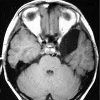

Хирургическое лечение арахноидальных кист. Иссечение кисты или удаление ее содержимого для формирования системы дренирования спинномозговой жидкости. Операция показана при наличии осложнений, в том числе сдавления окружающих тканей мозга с появлением неврологических симптомов, развитием гидроцефалии, появлением эпилептических импульсов, абсцесса, кровоизлияний. Хирургическое лечение арахноидальной кисты проводится через апертуру трепана с использованием современных методов через небольшое отверстие в мельнице. Дренирование кисты происходит через поток жидкости в субарахноидальное пространство, камеру мозга или правое предсердие.

Современное хирургическое лечение арахноидальных кист в неврологии осуществляется с помощью нейронавигационных систем по эндоскопической методике, которая менее травматична и не требует краниотомии. Для этой операции достаточно небольшого разреза кожи и одного отверстия в черепе. После вскрытия твердой мозговой оболочки и паутинной оболочки киста открывается, из нее удаляется жидкость. При вентрикулоскопии стенки арахноидальной коры перфорированы, а ее полость сообщается с субарахноидальным пространством и / или желудочком головного мозга. Дренирование кисты может быть выполнено с использованием металлического зажима с памятью формы. Для того чтобы войти в полость черепа через трехальное отверстие, протектор охлаждается и сгибается, и, попав в тело пациента и нагретый до температуры тела, приобретает заранее заданную форму.